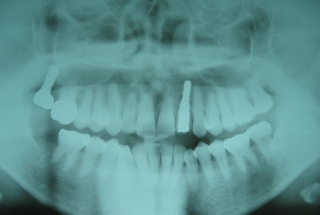

初診時年齢52歳。上顎前歯部欠損部インプラント治療前の咬合改善目的に来院。

インプラント治療は専門医にて行った。